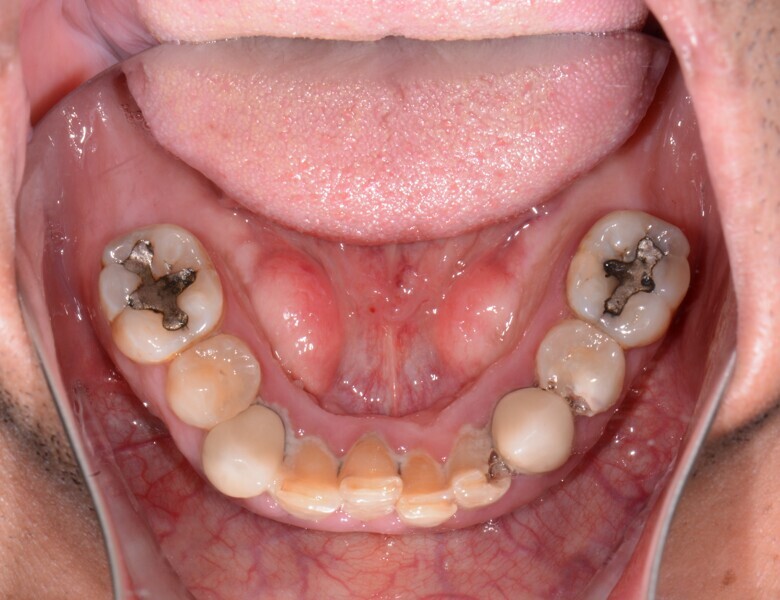

Fig. 3: Pre-op mandibular occlusal view.